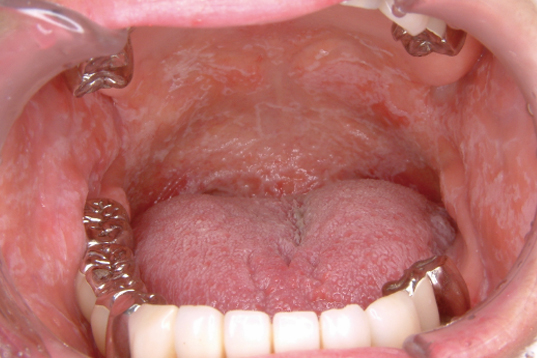

口腔の感染症には一般的な細菌を起因菌とする感染症だけでなく、カンジダやヘルペスといった特異的な微生物による感染症もあり、特に口腔のカンジダ感染症は頻度が高く留意が必要である8)。カンジダ感染症の典型的な症例では、粘膜上に白色~黄色の偽膜を形成することが多い。

上野尚雄先生ご提供